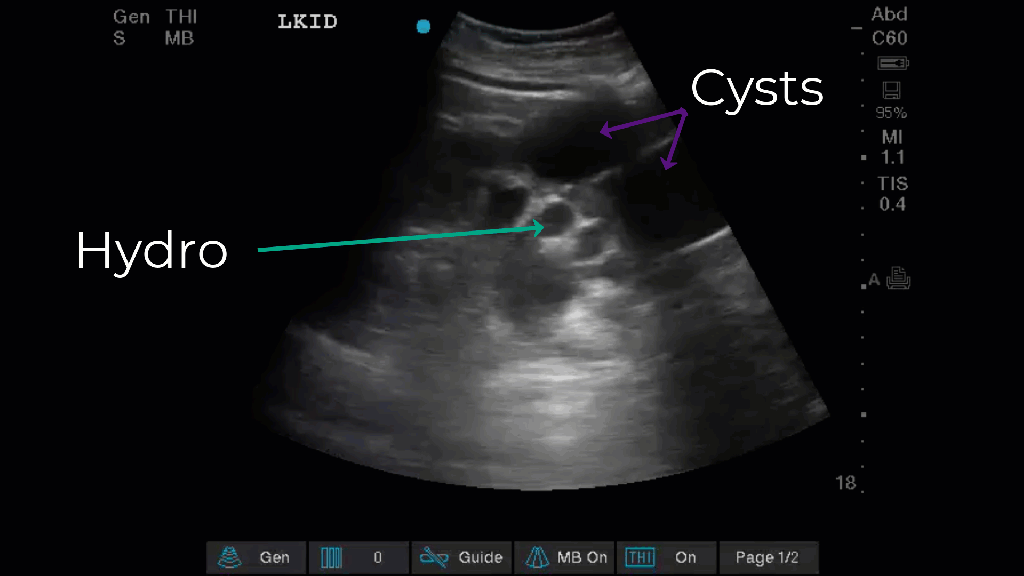

Renal Cysts: One of the false positives of hydronephrosis are cysts arising from the cortex or the even more confusing medullary cysts. The key in either case is to look at the renal pelvis if its not anechoic there its not hydronephrosis. In the example on the left the patient has BOTH hydronephrosis and cortical cysts so you can see the difference side by side.